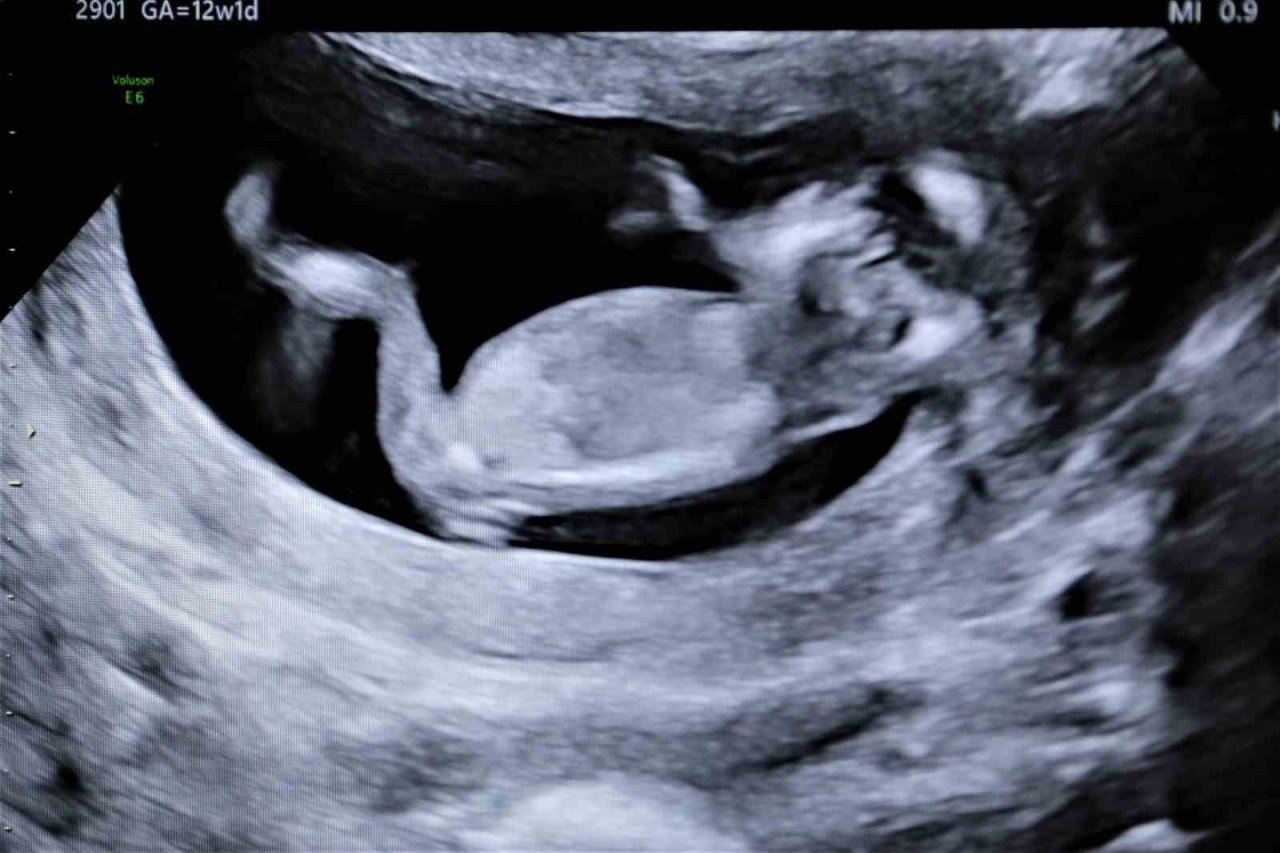

’Gebelikte her balığın eti yenmez’ uyarısı

Anne adayları için tüketilmesi gereken sağlıklı gıdalar kadar, tercih edilmemesi gereken gıdalar da önemli. Uzmanlara göre, gebelikte bazı balıkların yenilmesi bebeklerde sorunlara neden olabiliyor. Örneğin cıva miktarı yüksek olan, köpek balığı, kılıç balığı gibi ürünlerdeki cıva, plasentadan bebeğe geçerek bilişsel becerileri, motor becerileri, dil becerileri ve görme yeteneği üzerinde olumsuz etkiler yapabilmektedir.

"Gebe kalmadan 3 ay önce folik asite başlar ve gebeliğin 3'üncü ayına kadar devam ederse bebekte beyin omurilik sıvı defektleri yüzde 50 azalabilir. Bunu mutlaka yapmak lazım. Protein kaynaklarını çok iyi almaları gerekir. Aynı zamanda omega 3 bebeğin beyin gelişimi açısından da çok önemlidir. Kesinlikle haftada 2-3 porsiyon balık tüketilmelidir. Normal sezon balıkları tüketilebilir" şeklinde konuştu.

Hamilelikle folik asitin önemi hakkında bilgi veren Kumru, "Folik asit eksik olması durumunda sorunlu gebelik olabiliyor. Gebe kalmayı düşünendenler gebelikten en az 4 ay önce 0,4 miligram kullanmaya başlamalıdır. Gebeliğin 12'nci haftasına kadar devam edecek. Uzak durulması gerekenler ise deniz ürünlerinin bir kısmından uzak durulması gerekir. Dipte yaşayan deniz ürünleri bünyelerinde cıva barındırabilirler. Cıva bizim gebelikte istemediğimiz bir şeydir. Bebekte cıva zehirlenmesi olabiliyor" sözlerine yer verdi.